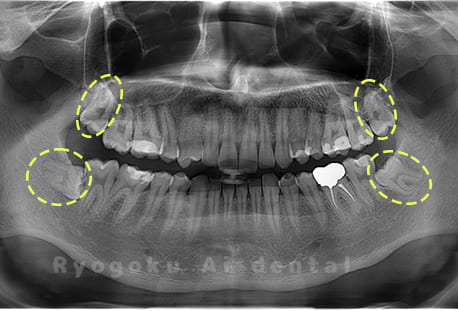

Case03

- 原因

- 上顎、下顎の親知らず

- 治療内容

- 上下4本の親知らずを抜歯したケースです。

<リスク・副作用>

手術後は痛み、腫れ、痺れなどの副作用が生じる場合があります。